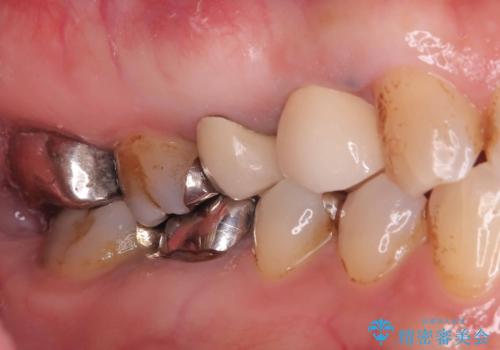

- 「2か月前から歯に違和感があるので診て欲しい」を主訴に来院された患者様です。

被せ物がコア(土台)ごと取れておりかつ根っこも折れてしまっている(歯根破折)状態でした。

歯根破折により保存は不可と診断し抜歯後、骨ができるのを待ってインプラントで治療を行いました。